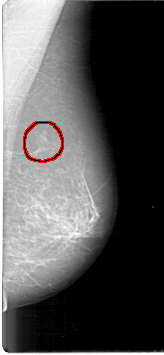

D_4097_1.RIGHT_MLO

FILE: D_4097_1.LEFT_MLO.OVERLAY

TOTAL_ABNORMALITIES 1

ABNORMALITY 1

LESION_TYPE MASS SHAPE IRREGULAR MARGINS ILL_DEFINED

ASSESSMENT 2

SUBTLETY 3

PATHOLOGY BENIGN

TOTAL_OUTLINES 1

BOUNDARY